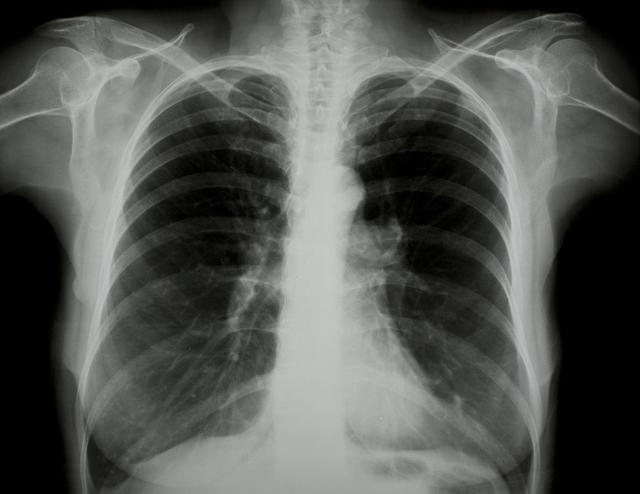

涪陵地區(qū)最新肺炎情況顯示,疫情形勢(shì)嚴(yán)峻。目前,當(dāng)?shù)卣歪t(yī)療部門(mén)正在積極應(yīng)對(duì),采取一系列措施控制疫情傳播。具體感染人數(shù)、癥狀表現(xiàn)、疫苗接種情況等仍在持續(xù)更新中。請(qǐng)廣大市民密切關(guān)注官方發(fā)布的信息,做好個(gè)人防護(hù),共同抗擊疫情。涪陵地區(qū)肺炎疫情嚴(yán)峻,政府積極應(yīng)對(duì),請(qǐng)市民關(guān)注官方信息,加強(qiáng)個(gè)人防護(hù)。